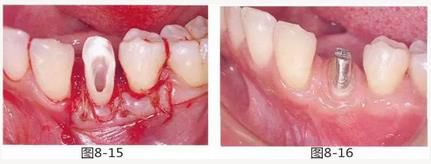

圖8-15 用齦瓣覆蓋結(jié)締組織瓣。

圖8-16 取模時修復(fù)體的狀態(tài)。牙齦溝約1mm,附著齦增加。